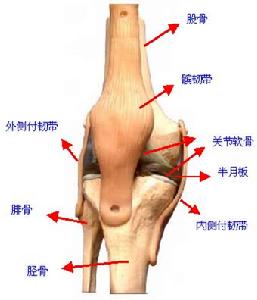

(1)扭傷指間接暴力使肢體和關節周圍的筋膜、肌肉、韌帶過度扭曲、牽拉,引起損傷或撕裂。多發生在關節及關節周圍的組織。

(2)挫傷指直接暴力打擊或衝撞肢體局部,引起該處皮下組織、肌肉、肌腱等損傷。以直接受損部位為主。頸、肩、肘、腕、指間、腕、膝、跺、腰等部位都可引起扭挫傷。其中腰部扭挫傷是最常見的腰部傷筋疾患,多見於青壯年。跌打損傷輕者傷及肌膚,多於短期內痊癒,只用通常膳食治療即可;重者傷筋動骨,創面污染,或出血過多,而致血虛氣衰,甚至傷及內臟,生命垂危,病期較長,則需膳食治療輔佐。